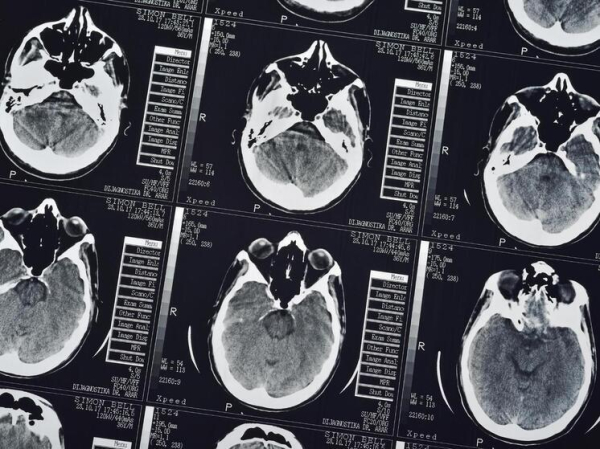

В эксперименте приняли участие 93 здоровых добровольца. Им наносили на разные участки тела (лицо, руки, ноги) обычный крем, который представляли как мощное обезболивающее, и одновременно тайно снижали интенсивность болевого теплового воздействия. Это классическая модель индукции плацебо-эффекта: до 61 процентов участников сообщали о значительном уменьшении боли именно в той области, где был нанесен «анестетик». Для сканирования мозга использовался один из самых мощных в Австралии 7-тесловый МРТ-сканер, позволивший увидеть активность с высочайшим разрешением.